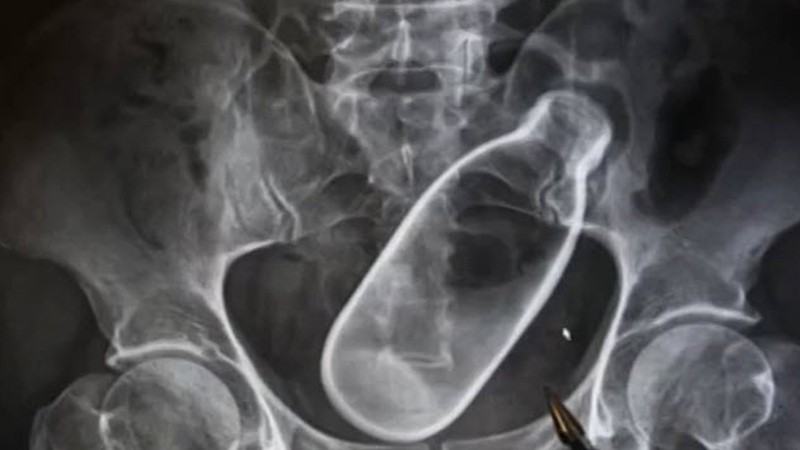

Уг хэрэг мөн л Хятадад болжээ. 2017 онд шулуун гэдэснийхээ амсарт шил хийж гацаасан нэгэн эрэгтэй түргэн тусламжаар эмнэлэгт ирсэн байна. Тэрбээр эмнэлэгт ирэхээсээ өмнө бүтэн хоёр өдрийн турш шилийг гаргаж авахаар янз бүрийн аргаар оролдсон бөгөөд үр дүнд нь шулуун гэдэс нь хавдсанаас шил хагарчээ.

Тус шил нь 7 см диаметртэй байсан бөгөөд эмч нар шилийг гараар авах боломжгүй байсан тул яаралтай мэс засал хийн биенээс нь гаргасан байна. Хагалгааны дараа өвчтөний биеийн байдал сайжирсан бөгөөд ямар ч зовуургүй эдгэжээ.